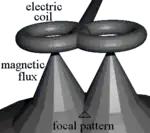

Coil types

Most devices use a coil shaped like a figure-eight to deliver a shallow magnetic field that affects more superficial neurons in the brain.[9] Differences in magnetic coil design are considered when comparing results, with important elements including the type of material, geometry and specific characteristics of the associated magnetic pulse.

The core material may be either a magnetically inert substrate ('air core'), or a solid, ferromagnetically active material ('solid core'). Solid cores result in more efficient transfer of electrical energy to a magnetic field and reduce energy loss to heat, and so can be operated with the higher volume of therapy protocols without interruption due to overheating. Varying the geometric shape of the coil itself can cause variations in focality, shape, and depth of penetration. Differences in coil material and its power supply also affect magnetic pulse width and duration.[32]

A number of different types of coils exist, each of which produce different magnetic fields. The round coil is the original used in TMS. Later, the figure-eight (butterfly) coil was developed to provide a more focal pattern of activation in the brain, and the four-leaf coil for focal stimulation of peripheral nerves. The double-cone coil conforms more to the shape of the head.[33] The Hesed (H-core), circular crown and double cone coils allow more widespread activation and a deeper magnetic penetration. They are supposed to impact deeper areas in the motor cortex and cerebellum controlling the legs and pelvic floor, for example, though the increased depth comes at the cost of a less focused magnetic pulse.[12]